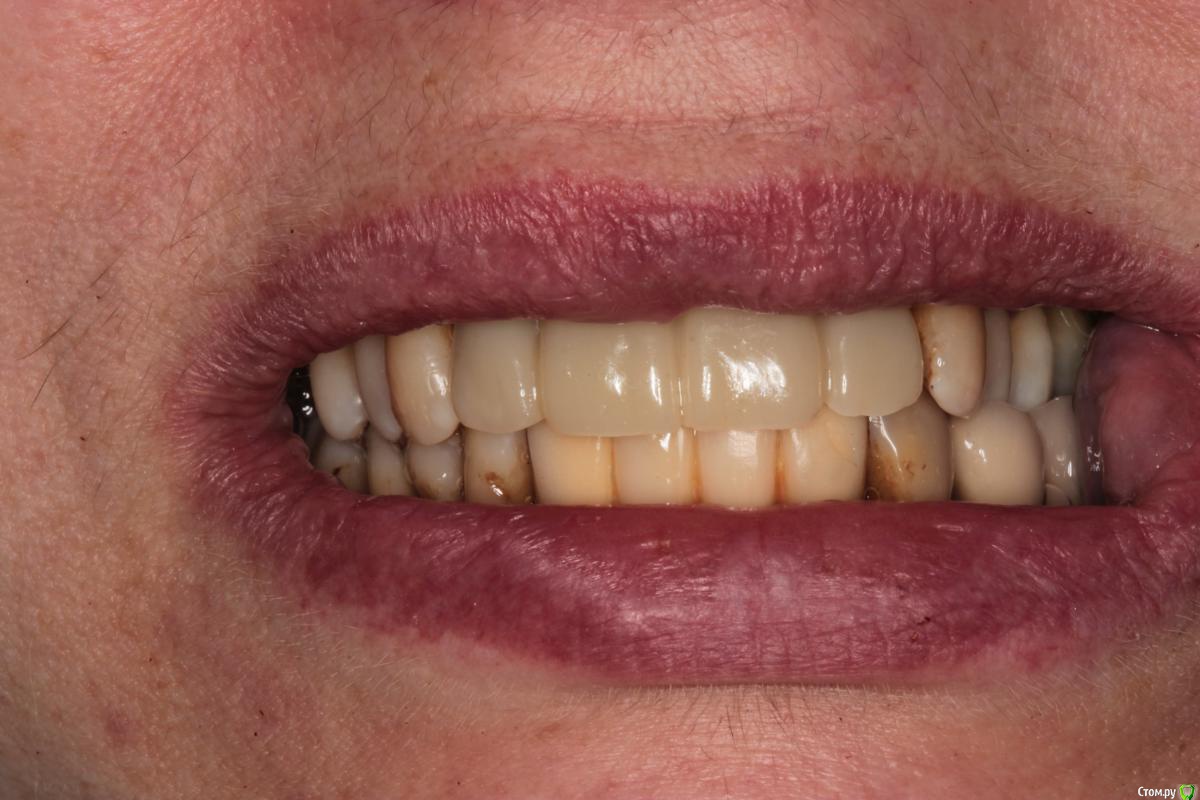

Abuk Опубликовано 27 ноября, 2015 Поделиться Опубликовано 27 ноября, 2015 (изменено) 1.bmp2.bmp3.bmp4.bmpЛечение.Альгинатные слепки,восковая моделировка.Удаление зубов и имплантата,удаление грануляций.Установка имплантатов,заполнение лунок графтом.сст,Времяхи по ключу. Изменено 27 ноября, 2015 пользователем Abuk 13 Ссылка на комментарий

Abuk Опубликовано 29 ноября, 2015 Автор Поделиться Опубликовано 29 ноября, 2015 (изменено) 1 е фото -"до", после были слепки и гигиена.Непосредственно перед имплантацией нет.Гигиена не фонтан,условились на том что первый год приходит каждые 3 месяца(осмотр и ггигиена),а там далее смотрим. Изменено 29 ноября, 2015 пользователем Abuk Ссылка на комментарий